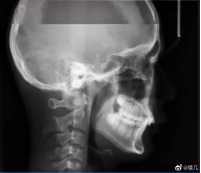

拍牙片時(shí)打了個(gè)哈欠,變成了毒液?用3D打印技術(shù)制作牙齒的好處

小編看到牙片表示:恐怖片果然來(lái)源于生活。有網(wǎng)友會(huì)問(wèn)3D打印技術(shù)能制作牙齒嗎?小編告訴你:可以!那么用3D打印技術(shù)做牙齒有哪些好處呢?

3D打印首次用于牙科時(shí),牙科實(shí)驗(yàn)室主要是打印模型和手術(shù)導(dǎo)向器,而不是留在患者身上的產(chǎn)品。如今,3D打印技術(shù)正在利用增材制造來(lái)創(chuàng)造出持久且精確定制的優(yōu)質(zhì)產(chǎn)品,以滿足每位患者的需求。牙科3D打印技術(shù)由于研究機(jī)構(gòu)和私營(yíng)公司不斷發(fā)展,涵蓋了牙科的各個(gè)方面。3D打印一顆牙齒只要三分鐘,比傳統(tǒng)的制作方法快了十倍,而且3D打印的質(zhì)量更高,因?yàn)樵撓到y(tǒng)在繪制牙齒結(jié)構(gòu)方面做的更好。